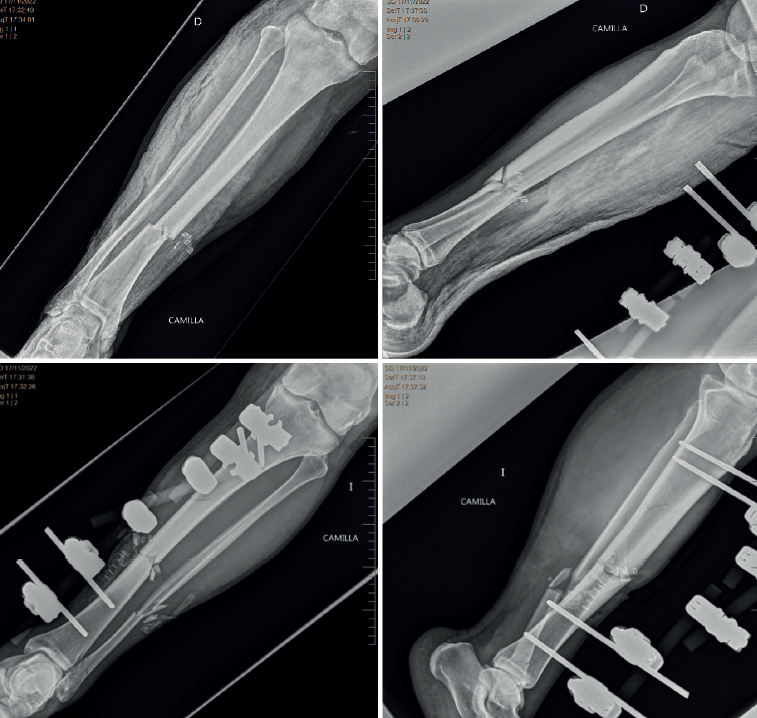

Acude a nuestro hospital derivado del servicio público de salud con un fijador externo Galaxy® tibial izquierdo y férula inguinopédica en el miembro inferior derecho (Figura 1).

Una vez estabilizado, el paciente vuelve a nuestro centro. Se realiza en dos tiempos la retirada del fijador externo inicial y se coloca TSF en ambas piernas. Al alta, el paciente pudo comenzar a hacer carga parcial de ambas piernas (Figuras 2 y 3).